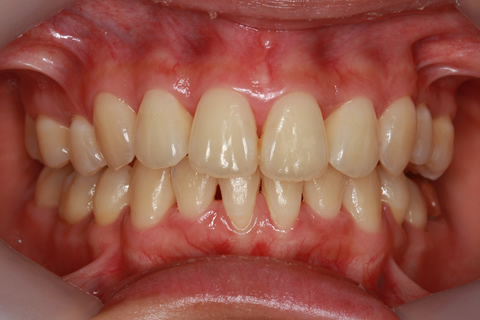

症例

治療前

治療中

治療後

- 年齢・性別

- 30歳女性

- 治療期間

- 3年0ヶ月

- 抜歯

- 上下左右4番抜歯

- 治療費

- 110万円

- 備考

- マルチブラケットを用いた矯正治療

- 治療内容

- 上下顎前突を4本抜歯にて矯正治療

- 施術の副作用(リスク)

- 表側矯正と比較して、歯根の角度を確立する「トルク」の力がかかりにくい。